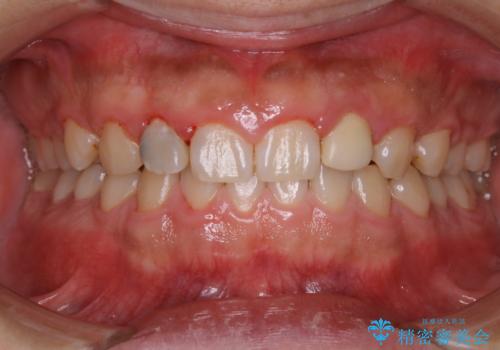

20年ぶりのクリーニングということもあり、歯の表面全てにプラークが付着していました。

プラークの細菌によりかなり歯ぐきが腫れていました。1度のクリーニングで汚れは落とせますが、このまま何もしないとまた同じようにプラークが付着し、それを繰り返すことになるだけでなく、歯周病や虫歯が進行してしまいます。そうならないためには、日々のケア、ホームケアがとても大事になっていきます。